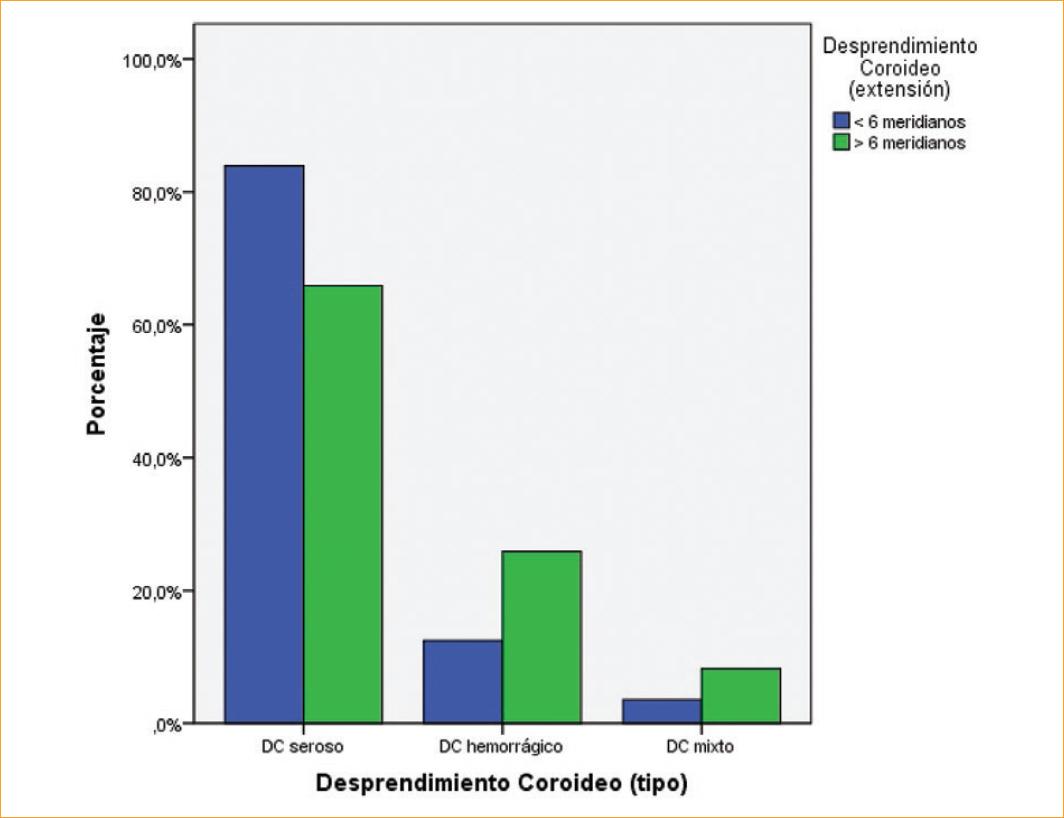

Del total de 141 casos analizados, 85 casos ocuparon más de 6 meridianos y 56 casos menos de 6 meridianos.

Cuando se los analizó según el tipo de desprendimiento, de los 56 casos con una extensión menor a 6 meridianos, 47 (83.9%) eran DC serosos, 7 (12.5%) DC hemorrágicos y 2 (3.6%) correspondían a DC mixto. En los 85 casos con una extensión mayor a 6 meridianos, 56 (65.9%) eran DC serosos, 22 (25.9%) DC hemorrágicos y 7 (8.2%) DC mixtos (Fig. 2).

Figura 2 Distribución de la extensión del desprendimiento coroideo (DC) según su antecedente. Pacientes evaluados en el Instituto de Oftalmología Fundación Conde de Valenciana, IAP, de enero 2015 a diciembre 2017.

Generalmente, el DC seroso plano no se extiende posteriormente hacia el ecuador, mientras que el DC hemorrágico puede extenderse hasta el polo posterior1. En nuestro estudio encontramos también una mayor extensión en los DC hemorrágicos comparativamente con los DC serosos, en que la extensión fue menor.

Los desprendimientos coroideos serosos suelen tener una extensión menor a 6 meridianos y los desprendimientos coroideos con contenido hemático y/o mixtos muestran una extensión mayor.